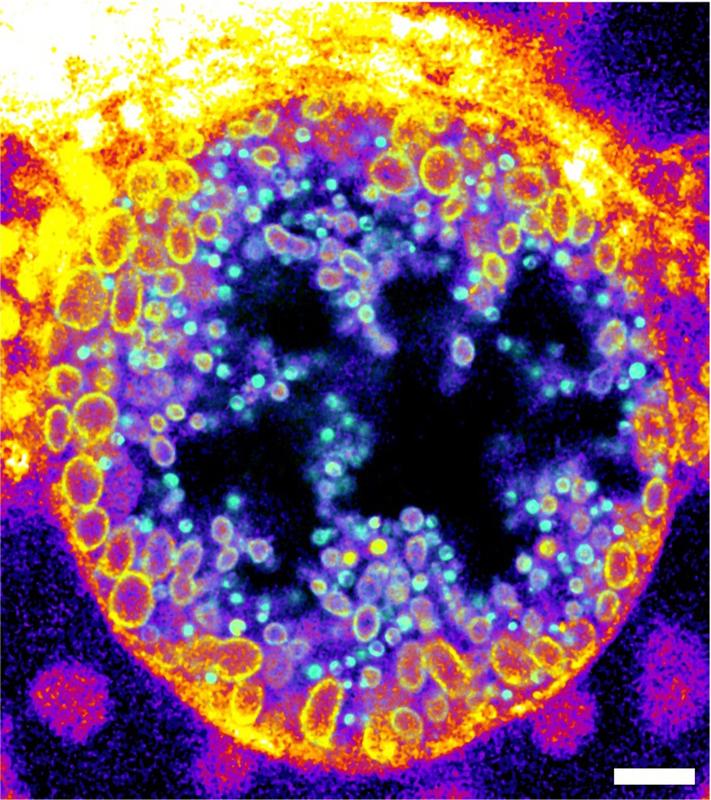

The scientists demonstrated the function of their newly developed molecules not only by determining the activity of a bacterial sphingomyelinase on the surface of human cells. They also visualised sphingomyelin degradation within human cells during the course of an infection with intracellular Chlamydia bacteria, which are known to infect the human genital tract and are suspected to contribute to the development of cancer in infected tissues.

Within their host cells Chlamydia form a replicative organelle called an inclusion. The researchers showed that chlamydial inclusions mainly contain the cleaved forms of the trifunctional sphingomyelins. Using so-called expansion microscopy and click-chemistry, they observed that the proportion of metabolised sphingomyelin molecules increased during the maturation of non-infectious to infectious Chlamydia particles. By being able to visualise this infection process new targeted strategies against these infections can now be developed.